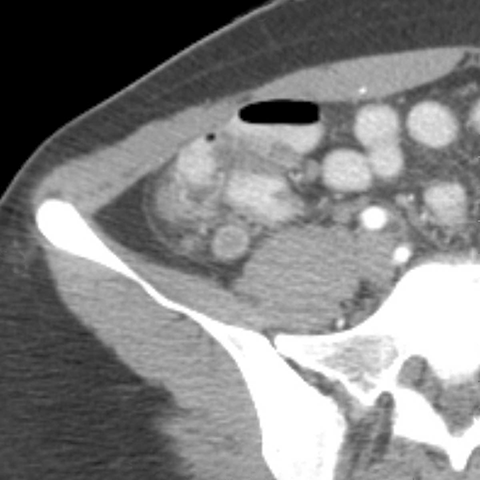

18 year-old male presents with a sudden onset of RLQ pain and rebound tenderness. [2 of 5]